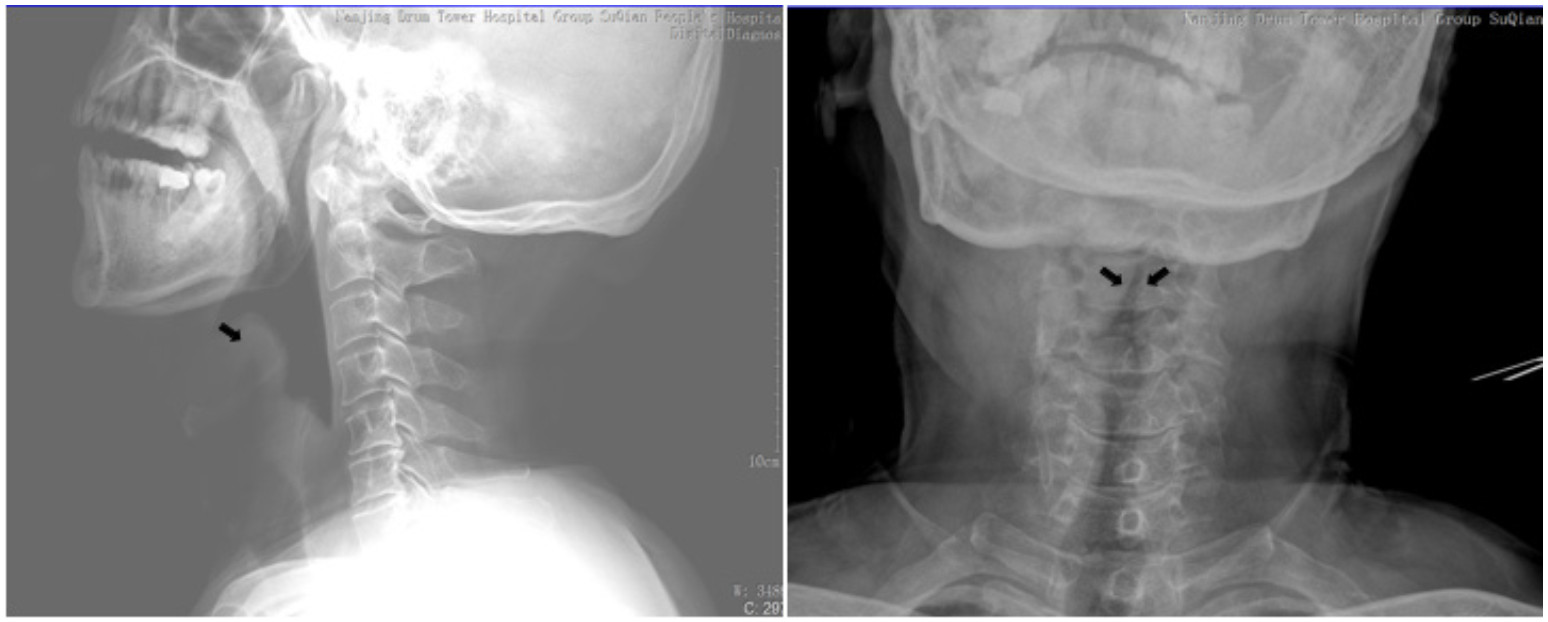

1 病例资料患者,男,58岁,因“咽痛9 h,加重伴胸闷1 h”急诊入院。患者于2020年4月1日下午13时出现咽痛、低热伴全身不适症状,咽部堵塞感。自服头孢拉定、牛黄上清片等药物咽痛症状无好转,18时因咽痛加重,吞咽时疼痛明显,曾尝试再次口服抗生素等药物,但由于吞咽困难持续存在,因此无法吞服。晚间患者咽部疼痛加剧伴流涎,无法忍受吞咽唾液,说话含糊不清,阵发性胸闷不适。遂于22:30至徐州医科大学附属宿迁医院急诊科就诊。急诊室进行体格检查:体温38.8 ℃,急性痛苦面容,扁桃体无明显肿大,咽后壁外观未见明显异常,颈部亦无明显肿胀的迹象,触诊无触痛,心肺听诊未见明显异常。急诊遂行颈、胸部CT及X线检查。颈部及胸部CT提示:会厌皱襞明显增厚伴喉室腔显著狭窄,慢支、肺气肿;颈部X线提示:会厌显著增厚,拇指征阳性(图 1、图 2)。急诊考虑“急性喉头水肿”遂予以急诊留观,给予甲强龙500 mg静脉滴注,同时予吸氧、监护等处理。鼻导管4 L/min时患者的外周血氧饱和度(SpO2)在95%左右。联系耳鼻喉科急诊会诊。

| 图 1 颈部正侧位片显示会厌显著增厚呈拇指征及塔尖征(黑色箭头) |

急性会厌炎的高病死率被认为与诊断延迟和治疗不当有关,早期最常见的主诉是咽喉痛和吞咽困难,常归因于上呼吸道感染。大多数病例在死亡前至少4 h出现呼吸系统症状的症状,并且在崩溃之前突然发生了急性呼吸急促。抢救时,在最短时间内,重建呼吸通道对挽救患者生命十分重要,以免失去抢救时机,因此如何早期识别危重患者及时的干预十分重要。气道干预因素中相关的临床症状包括[7-8]:呼吸困难、流涎、喘鸣和坐直和呼吸困难[9]。此外,年龄较大,男性,体重指数25 kg/m2以上和糖尿病增加了进行气道干预的必要风险[10]。实验室器械检查方面鼻咽镜及视频喉镜是声门上炎最可靠、最准确的诊断和评估工具,可以非常直观的判断会厌及周围组织的水肿程度[11],但侧面软组织放射线的拇指征可提供无创性诊断[12-13],Fujiwara等[14]发表的Meta分析结果表明,拇指征兆的特异度为89.2%,敏感度为92.2%。但急诊室的会厌炎患者包括喉镜和气道手术在内的临床干预措施的文献记录极少。一项对美国2007年至2014年33 549例急性会厌炎患者的样本研究,在急诊室中,仅 < 1%接受过喉镜检查。X射线和计算机断层扫描的检测率均小于10%[15],X线、计算机断层扫描及喉镜检查的低检测率反映了医生可能未能充分认识到会厌炎评估及早期气道干预的必要性。有必要进行进一步的研究急诊可视化检测低的原因,以提高急性会厌炎在急诊可视化的检测率,从而进行更及时的干预,以防止会厌炎的死亡[16]。

本例患者颈部X线提示会厌显著增厚,拇指征及塔尖征阳性(图 1),计算机断层扫描显示会厌皱襞明显增厚伴喉室腔显著狭窄(图 2)均提示病情危重,为临床干预提供可靠的依据。因此对于重症急性会厌炎的临床特点及危险性应有足够的认识,呼吸困难、流涎、喘鸣和坐直和呼吸困难重症急性会厌炎需要气道干预主要相关因素。本例患者因咽痛、吞咽困难、流涎、说话含糊不清等症状就诊,值班医生亦考虑到会厌炎可能,完善了CT及X线检查后很快出现严重的吸气性呼吸困难,躁动不安,血氧饱和度快速进行性下降,因患者黏痰较多,强迫半坐位无法平躺,在影像确诊后仅数分钟就因气道梗阻发展到心脏骤停。因此遇到在此类重症急性会厌炎患者,在诊治流程上如患者出现吞咽困难、流涎、喘鸣和呼吸困难,应考虑到为需要紧急气道干预患者,紧急送抢救室完善急诊喉镜评估,为建立人工气道缩短时间,避免检查及转运过程中因窒息导致的心搏呼吸骤停。